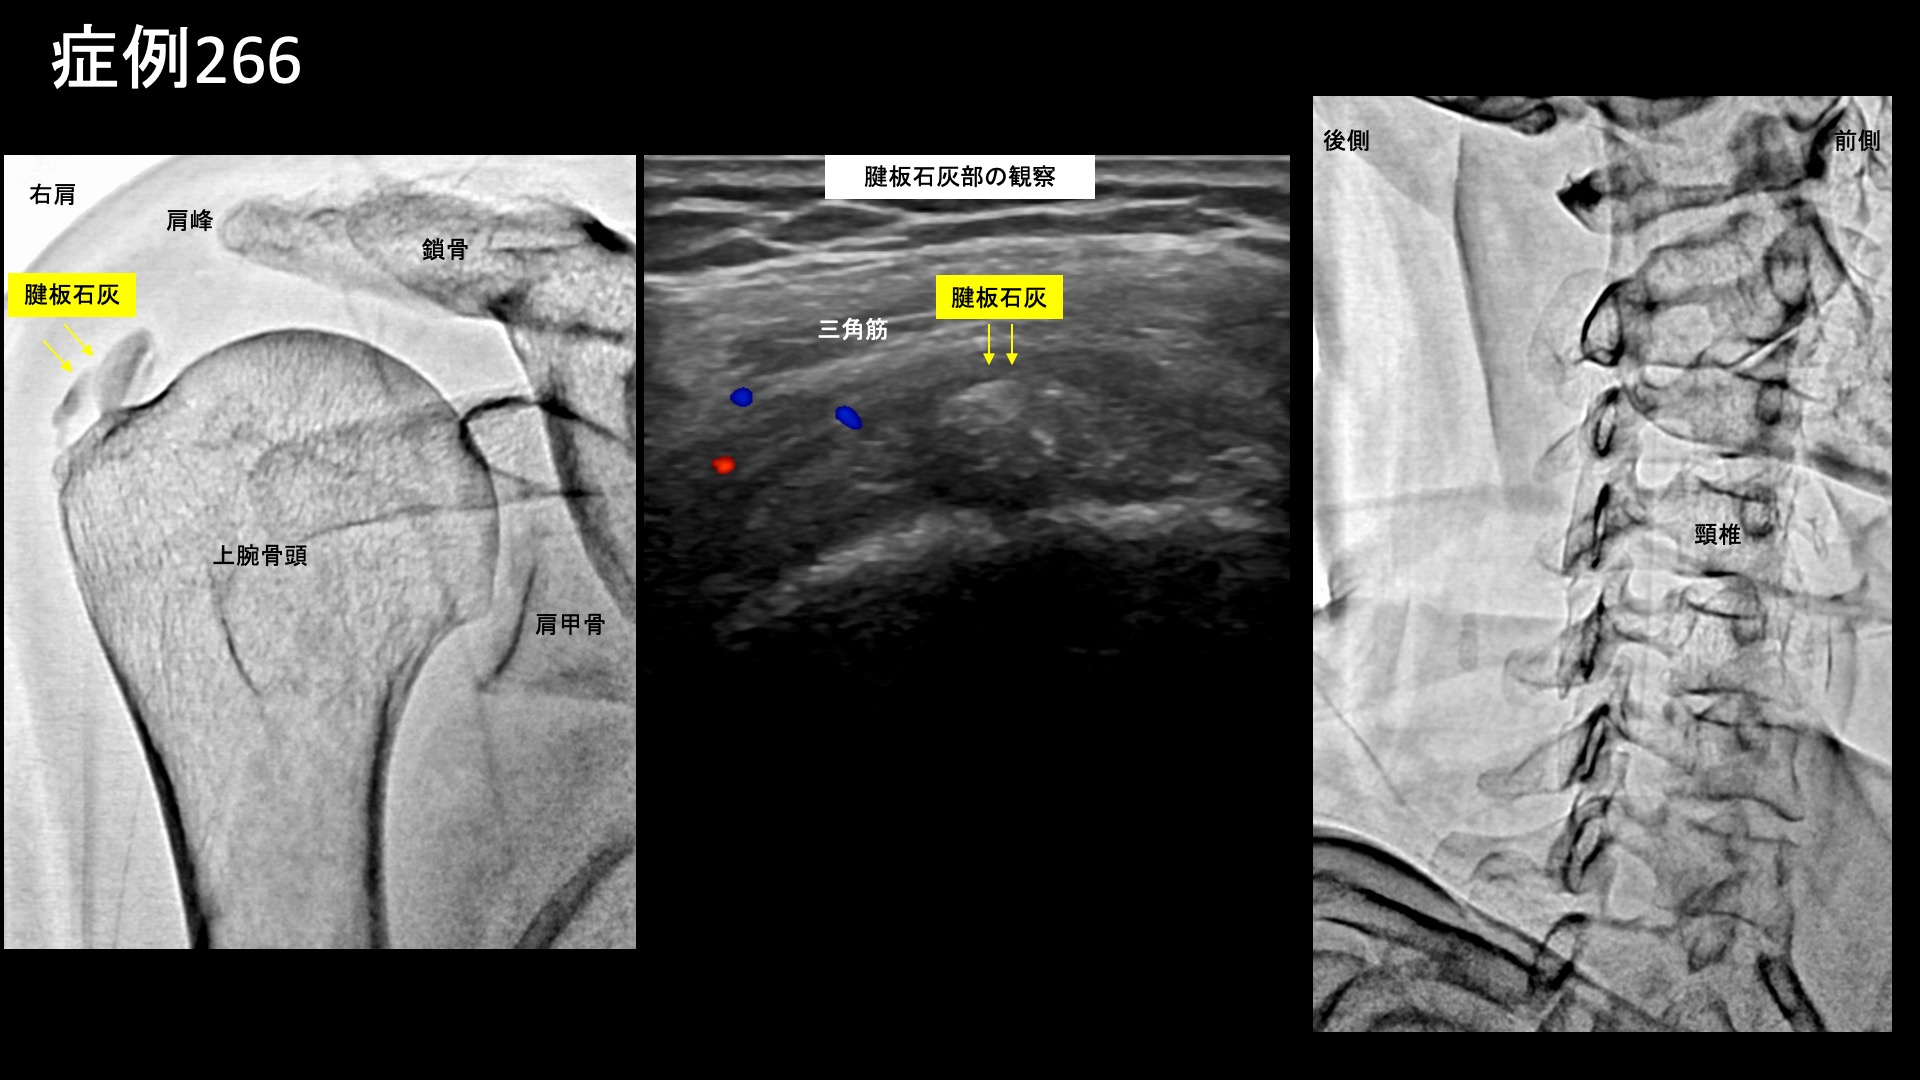

肩:肩こり・四十肩・五十肩 【50代:女性】1年以上悩まされた、石灰沈着性腱板炎による夜間痛を伴う右肩の痛み(石灰沈着性腱板炎、肩関節周囲炎) 2026.02.27 鴨井院長による動画解説 受診までの経過 4年前から右肩に痛みがありましたが、1年前から増悪し、夜間痛も伴うようになりました。整形外科では石灰沈着性腱板炎と診断され、ヒアルロン酸注射、ステロイド注射、リハビリの他、針による石灰吸引も何度か試みましたが改善せず、夜眠れないほどに悪化してきました。当院の治療を知り受診されました。 診察時の所見 ひどい夜間痛がある割に、右肩関節の可動域は保たれていました。前述の整形外科通院治療の効果によるものと思われました。レントゲンでは腱板部に石灰沈着を認め、同部位をエコーで観察したところ、石灰部周囲にモヤモヤ血管(病的新生血管)を反映した異常血流信号を認めました。その他、上腕二頭筋長頭腱周囲や腱板粗部においても同様に炎症所見を認めました。首肩こりの訴えもありましたが、後頸部には項靭帯石灰沈着を認めました。治療適応と判断し、モヤモヤ血管(病的新生血管)に対する運動器カテーテル治療(微細動脈塞栓術)を受けていただきました。 治療の所見 血管造影を行うと、首こりの主要責任血管である深頸動脈にてモヤモヤ血管が濃染像として描出されました。肩関節では、肩甲上動脈、胸肩峰動脈、烏口枝、後上腕動脈において同様にモヤモヤ血管が認められました。治療後は画像上速やかに消失しました。その他複数箇所の治療を行い終了しました。 治療後の経過 夜間痛は治療後すぐから消失し、寝られるようになりました。治療後2週間、動作時に上腕に痛みが出るほか、肩こりの痛みがまだ2か所に残っていましたが、全体的にはかなり改善してきました。治療後1ヶ月半、右上腕の痛みは消失しました。肩こり部位についてはデスクワークの際に痛む程度でした。その後肩への負担により痛みがぶり返したことがありましたが、注射加療のみで再び消失し、治療後4ヶ月時点で問題ないことを確認し終診となりました。 石灰沈着性腱板炎は、長期に経過していると石灰の器質化が進み、カテーテル治療により炎症を鎮めても吸収されることはなく残存します。ほとんどの場合、石灰が残っていても問題はありませんが、その大きさや分布によっては、インピンジメントの原因となることがあり、動作時痛が少し残ったり、周囲を刺激して新たな炎症を起こしたりすることがあります。ぶり返したのはインピンジメントによる可能性が高いです。刺激しないようにしている内に自然におさまることもありますが、インピンジメントの影響がしつこく疑われる場合は、外科的摘除が検討されます。保存的治療のみで完結させたい場合は、あまりに長期に放置しないよう、半年以内までにカテーテル治療を受けていただくことをおすすめします。 石灰沈着性腱板炎の詳細はこちら 【50代:女性】首がきしみ、肩はガチガチ、頭が重く、顎はカクカク・・2回のカテーテル治療により改善した重症首肩こりおよび頭痛・顎関節症(詳細説明あり)(首肩こり、頸肩腕症候群、頭痛、顎関節症、食いしばり(ブラキシズム)) 前の記事 【50代:男性】足首の外側(外くるぶし)が痛い、腓骨筋腱炎に対するモヤモヤ血管治療(腓骨筋腱炎、腱付着部症) 次の記事